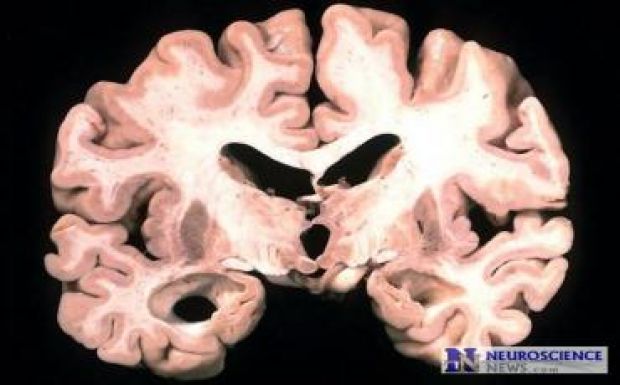

A demencia gyógyíthatatlan betegség, amely néhány fejlett országban már kezdi megelőzni a szívbetegséget a vezető halálokok között. A demencia az agy megbetegedése, leggyakrabban az Alzheimer-kór okozza. A mozgásképesség hanyatlásával, az emlékezet romlásával, a gondolkodás, a viselkedés megváltozásával, a tájékozódó képesség, a mindennapi tevékenységek elvégzéséhez szükséges képességek elvesztésével jár.